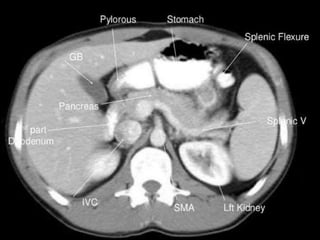

CT cross sectional anatomy.

CT – computedtomography. •Cross-sectional modality with capabilities for multiplanar reconstruction and dynamic imaging to assess vascularity •Tube rotates around the body and a circle of stationary detectors detects the penetrating x-rays forming an image.